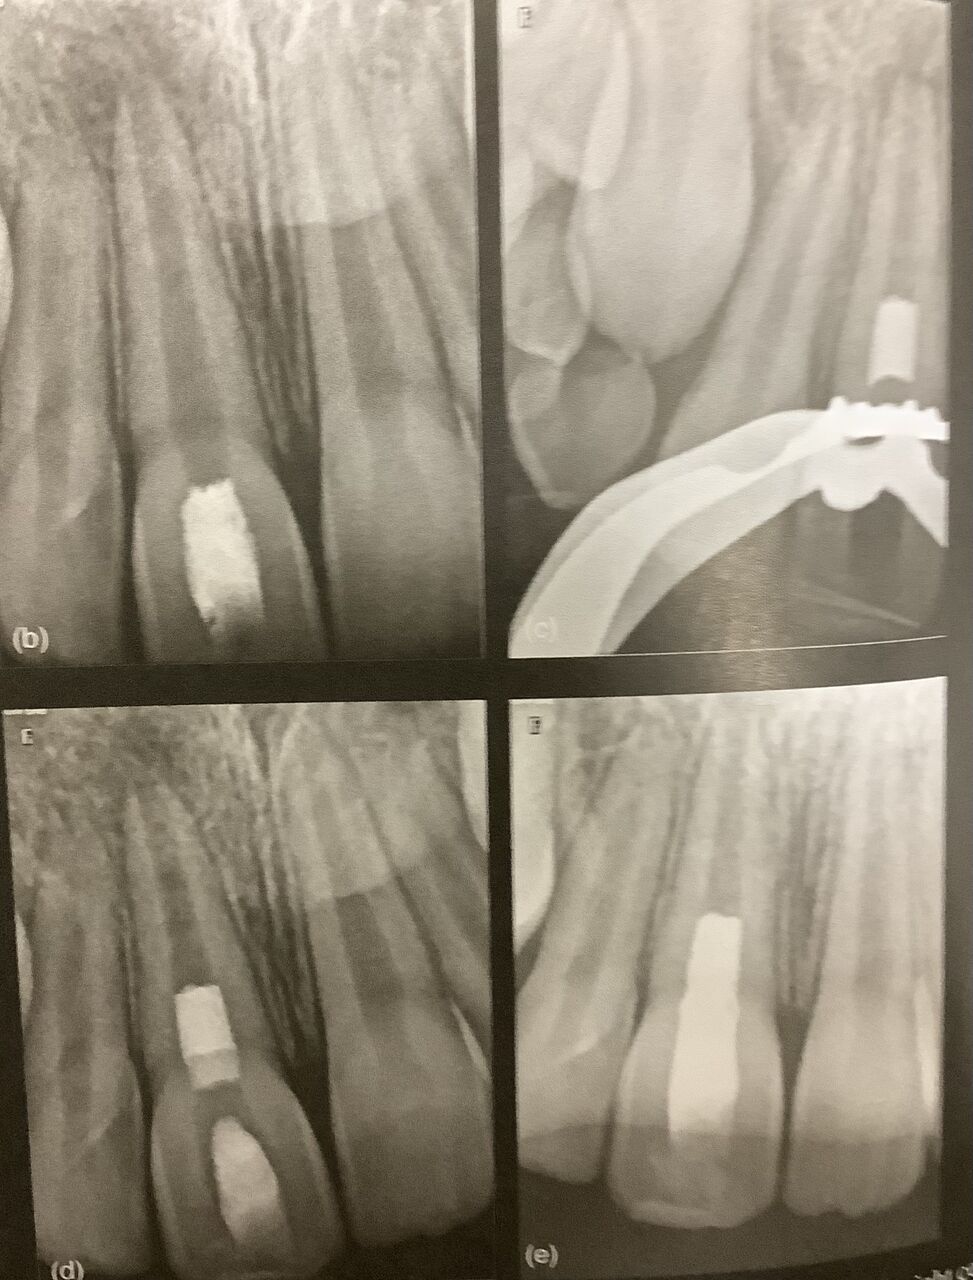

根っこの神経への入り口が見つかるように、神経の部屋の床部分を出します。

⚪︎上の方を真っ直ぐにする。

根っこの先まで無理なく器具が入るためにです。

上手なアクセスによって、神経の管が変な方向に削れたり、器具が折れたりするのを防げます。

最近は出来るだけ小さく削るのが注目されています。

出来るだけ多くの象牙質を残すためです。

神経の部屋の天井部分を多く残すことで、折れにくくなります。